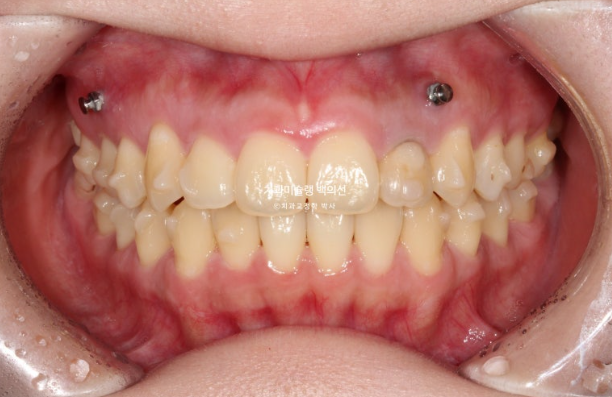

23년 12월 교정치료를 위해 멀리 지방에서 오신 환자분입니다.

23.12

환자가 고치고 싶은 것은 배열, 교합, 거미스마일(잇몸미소) 마지막은 비대칭 입니다.

엑스레이 검사 결과 뼈의 비대칭은 경미하나 상하 치아중심선이 어긋나있어서 이 부분 개선을 원하셨습니다.

교합은 거꾸로 물리는 어금니 반대교합도 있고, 뜨는 부분도 있고 앞니 하나는 신경치료 후 변색이 되어 있습니다.

작은어금니가 입천장으로 들어가 있어 반대교합 상태였습니다.

멀리 지방에서 오는만큼 내원간격이 중요해서 인비절라인으로 치료하기로 했습니다.

첫 세트 장치는 30개가 나왔으며 위 앞니 뿐만 아니라 어금니까지 전체치열을 후방이동하며 함입시키는 계획입니다.

교정용 나사와 고무줄을 이용하여 주도면밀한 치료계획하게 치료를 진행했습니다.